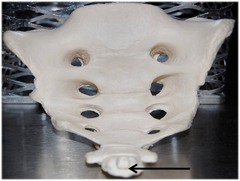

97

New cards

Coccyx

Name this specific bone.

98

New cards

Sacrum

Name this entire bone.